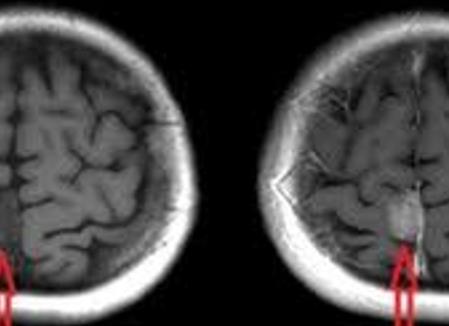

Магнитно-резонансная томография проводится с использованием специального аппарата, в который помещают пациента. Он излучает магнитные поля, которые проявляются высокочастотными импульсами. С их помощью специальное компьютерное ПО определяет состояние проверяемого аппаратом участка. При исследовании головного мозга после МРТ врач получает изображения с высокой степенью детализации, что позволяет максимально подробно его изучить.

Очень часто процедура проводится с введением в организм пациента контрастного вещества. Разница обычного МРТ и исследования с контрастом в том, что во втором случае медицинские препараты будут усиливать степень анализа мозга или другого органа человека, что позволит получить максимально точную информацию о патологии и быстро начать основное лечение.

Разница между МРТ головного мозга без контраста и с ним заключается в точности и детальности результата, который будет лучше в последнем случае. Магнитно-резонансная томография дает возможность сделать серию качественных снимков обследуемых органов и выявить патологические изменения.

Что же такое МРТ с контрастом? Обычно данный метод применяется для устранения сомнений относительно постановки диагноза или выявления злокачественных опухолей на ранних стадиях.

Особенность диагностики в − специальных веществах (парамагнетиках), отличающихся усилением отчетливости получаемой картины: поврежденные ткани окрашиваются в иной цвет, причем скопление контрастирующего вещества происходит преимущественно в участках, пораженных болезнью.

Парамагнетики чутко реагируют на воспаление и разрушение тканей, и без них труднее рассмотреть очаг заболевания, выявить рецидив, различить доброкачественность и злокачественность новообразования.